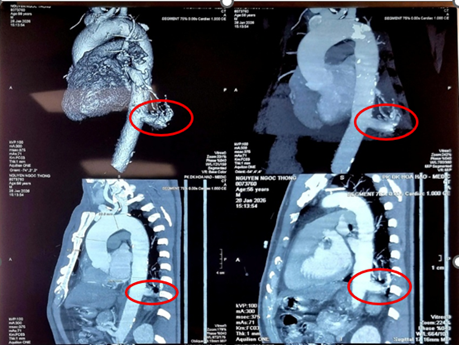

Hình chụp cắt lớp vi tính đa dãy ngực của bệnh nhân. Ảnh: BVCC.

Bệnh nhân là ông N.N.T. (56 tuổi, ngụ Tây Ninh), tình cờ phát hiện tổn thương thùy dưới phổi trái khi khám sức khỏe định kỳ. Tại Bệnh viện Bình Dân, các bác sĩ chẩn đoán người bệnh mắc phổi biệt lập nội thùy với khối kích thước 23x26 mm.

Đáng chú ý, động mạch nuôi khối này xuất phát trực tiếp từ động mạch chủ ngực xuống, đường kính lên tới 17 mm, tiềm ẩn nguy cơ chảy máu nghiêm trọng nếu không được xử trí kịp thời.